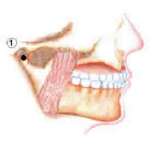

Zahnfleischschwund durch

Parodontitis: An allen Zähnen eines Kiefers -

hier am Oberkiefer - geht das Zahnfleisch

zurück, am Unterkiefer nicht.

Die empfindlichen Zahnhälse liegen nun zum

Teil frei und ungeschützt und sind

kariesgefährdet.